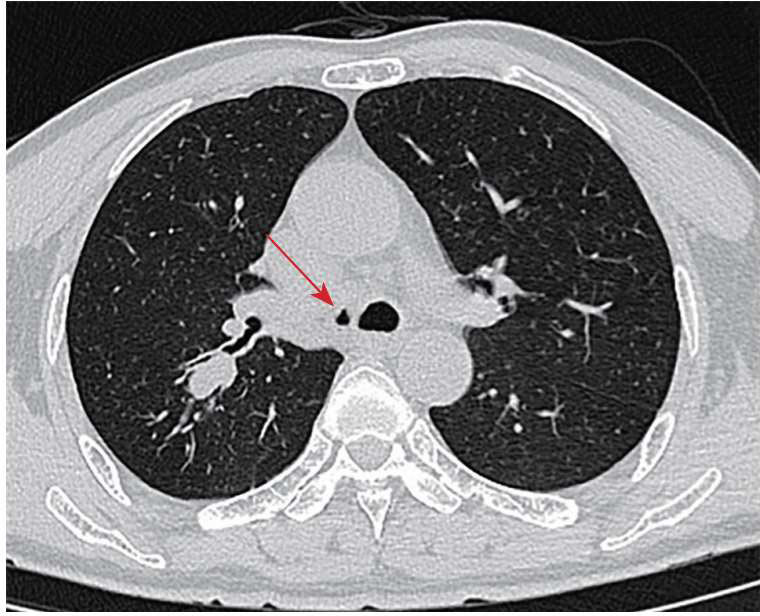

1.高风险人群: 对于肺癌高风险群体,如长期吸烟者、有家族肺癌史者、长期接触职业粉尘者等,医生会建议行胸部CT检查作为早期筛查手段。某些肺癌早期可能没有明显症状,而CT可以直接发现肺部微小的异常变化,可以发现新出现的肺结节或纵隔异常。当肺部结节增大时,可能出现压迫支气管,导致支气管狭窄。如果临床高度怀疑肺癌,医生常常会建议患者做支气管镜检查,可以在支气管镜下发现气管肿瘤病变,这样有助于早诊早治,大大提高治愈率。

胸部CT显示肺部结节和支气管狭窄(箭头所指)